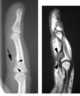

Soft-tissue chondroma